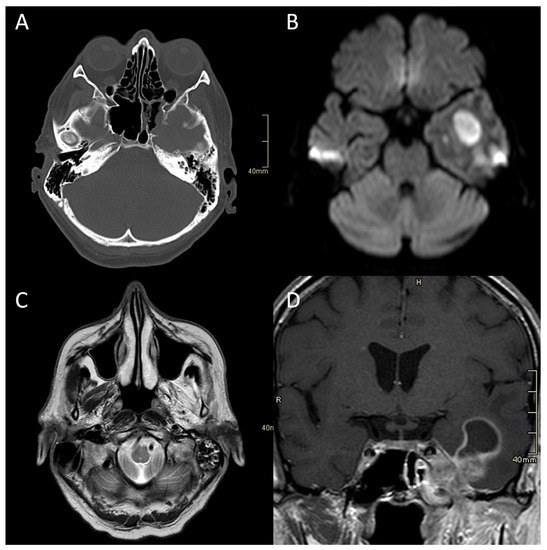

Figure 1.

CT and MRI of a patient with fungal atypical skull-base osteomyelitis due to acute invasive fungal sphenoid sinusitis. (A) Axial CT bone algorithm reconstruction showing erosion of the lateral wall of the sphenoid sinus, indicating the spread into the cavernous sinus and middle cranial fossa toward the Meckel’s cave. (B) Axial MRI DWI showing increased signal in the left temporal lobe. (C) Axial MRI T2 showing increased signal in left masticatory muscles due to the denervation corresponding to the damage of the trigeminal nerve. (D) Coronal CE MRI T1 showing the spread of the infection from the sphenoid sinus into the parasellar space, cavernous sinus, and Meckel’s cave, with an intraparenchymal abscess of the temporal lobe. CT: computerised tomography; MRI: magnetic resonance imaging; DWI: diffusion-weighted imaging; CE: contrast-enhanced.

CT is often the first imaging modality in patients with SBO as it is the most accessible and can be performed in the urgent setting. In addition, CT, especially high-resolution bone reformats, is the best way to assess the often subtle bone erosion and demineralisation characteristic of SBO [4,9,18,42]. Cortical erosions in ASBO are most often noted along the anterior clivus and foramina of the central skull base; in cases of invasive sinusitis, opacification and erosion of sinus walls can be noted, especially sphenoid sinus and ethmoid cells (Figure 1A, Figure 2A and Figure 3A,B) [6].

Imaging studies, both MRI and CT, including CTA and CTV, are essential in diagnosing complications of SBO. These include the intracranial spread of infection, the formation of an abscess, either intracranially (Figure 1B,D and Figure 4C,D) or in the soft tissues of the head and neck (Figure 2F,H,I), and vascular complications—venous thrombosis, venous or arterial stroke, and mycotic aneurism formation [30,46,47].